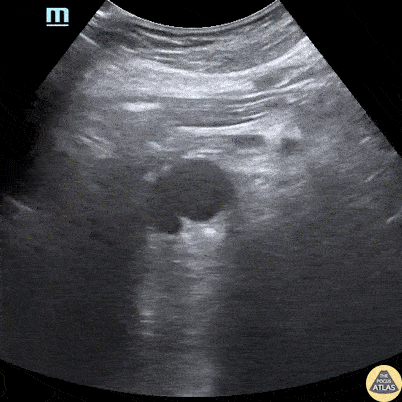

Aorta - Abdominal Aortic Dissection Flap

Patient with abrupt onset chest pain radiating to back. Normal ECG and Troponin. POCUS revealed dissection flap within abdominal aorta. Nishant Cherian Emergency Medicine Registrar